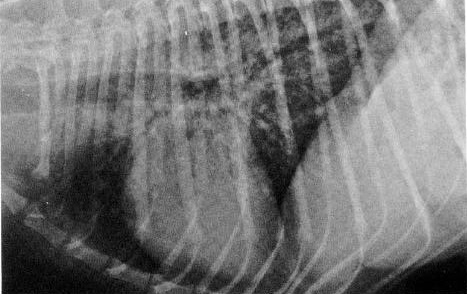

There

are several options available for diagnosis of PCP. An x-ray

should reveal a fine, net-like pattern of matter in the lungs, referred to as a

"generalized interstitial lung pattern" (see at left).